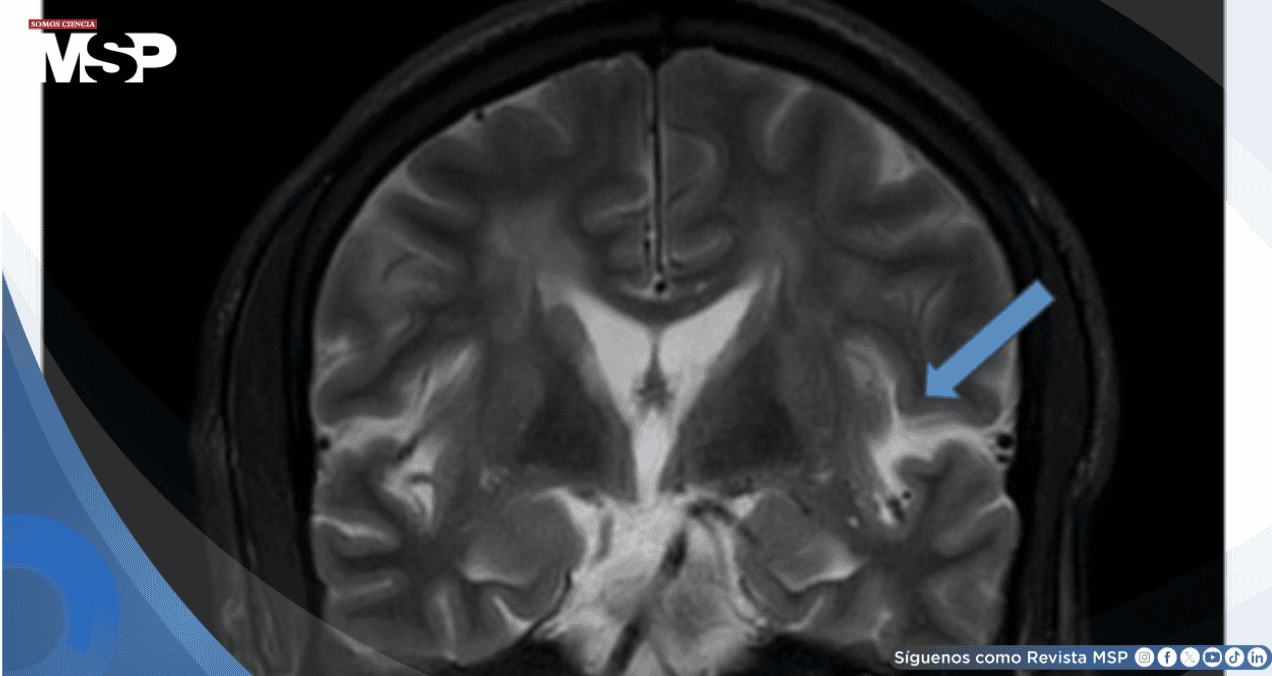

Se realizó resonancia magnética cerebral que demostró extensos parches de hiperintensidad en secuencias T2 y FLAIR distribuidos en el hemisferio cerebeloso izquierdo y regiones periventriculares y subcorticales bilaterales de ambos hemisferios, con predominio posterior.

Las secuencias de difusión (DWI/ADC) no mostraron restricción evidente. Las imágenes T1 con contraste revelaron realce leptomeníngeo parieto-occipital izquierdo. La angiorresonancia de vasos intracraneales descartó vasoespasmo, excluyendo el síndrome de vasoconstricción cerebral reversible.